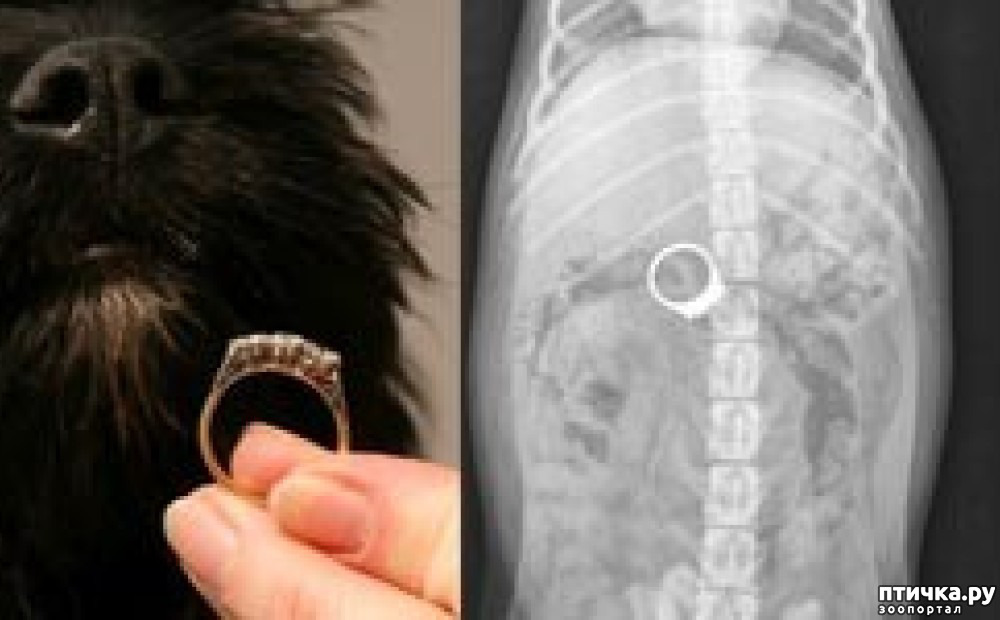

Потом почитала, что находят в желудках кошек: лучше не читать, а тем более не смотреть. Обычно самые тяжёлые случаи с длинными предметами: нитки, елочный дождик и т. п. Хотела приложить картинки, но решила не стоит, и так негативного столько... Просто надо быть внимательнее. А в качестве ещё одной хорошо закончившейся историей прикладываю фото проглоченного собакой фамильного кольца.